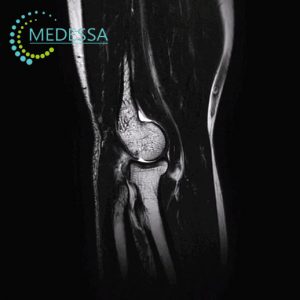

Магнітно-резонансна томографія (МРТ) суглобів та м’яких тканин — це високоточний метод медичної діагностики, який дозволяє детально візуалізувати анатомічні структури опорно-рухового апарату без використання іонізуючого випромінювання. Дослідження дає змогу оцінити стан колінного, плечового, тазостегнового, гомілковостопного, ліктьового, променево-зап’ясткового та інших суглобів, а також м’язів, сухожиль, зв’язок, менісків, фасцій та навколосуглобових тканин.

МРТ 3.0 Тесла в Одесі забезпечує максимальну деталізацію структур суглоба, що особливо важливо для раннього виявлення пошкоджень зв’язкового апарату, хрящової тканини та внутрішньосуглобових елементів. Високопольний томограф дозволяє діагностувати патології на ранніх стадіях, коли клінічні прояви можуть бути мінімальними.

Які структури візуалізує МРТ суглобів

- суглобовий хрящ;

- меніски;

- зв’язки;

- сухожилля;

- м’язи;

- синовіальна оболонка;

- суглобова капсула;

- кісткові структури;

- нерви;

- судини;

- бурси та фасції;

- навколосуглобові м’які тканини.